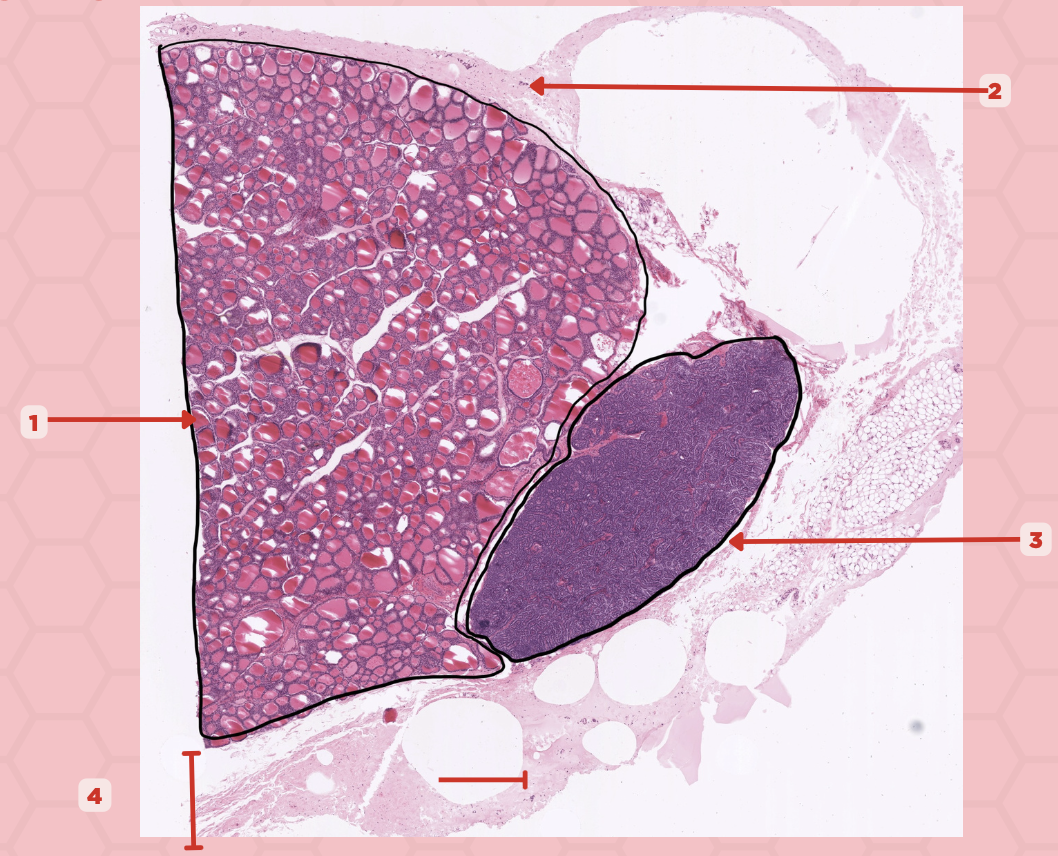

Thyroid-Parathyroid

Identify the specimen.

Thyroid Gland

Identify the structure labeled as 1.

Capsule

Identify the structure labeled as 2 and 4.

Parathyroid Gland

Identify the structure labeled as 3.